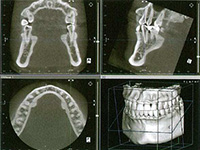

インプラント治療を始める前には、慎重な事前検査が必要になります。レントゲン撮影・CTスキャン・口腔内模型などによる十分な検査を行い、綿密な治療計画を立てます。患者さんの同意を得てから手術の日程を決めます。